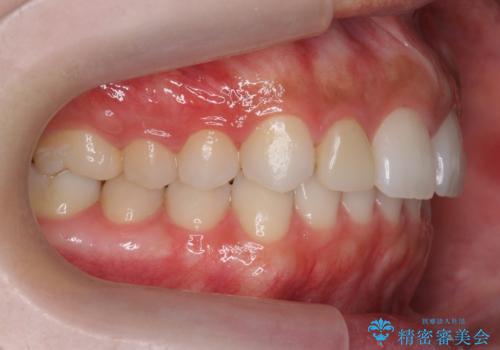

前歯が出っ歯ですきっ歯 抜かずに前歯を見た目良く

- 前歯の並びを主訴に来院。

前歯が出ており、また、左上の側切歯が1本生まれつき少ない状態でした。

また、右の奥歯の関係も上が前にある状態で大きくずれていました。

奥歯の関係を完全に1級にするには右上の小臼歯の抜歯が必要でしたが、もともと左上の前歯が生まれつき少ないため今回は歯を抜かずに治療しています。